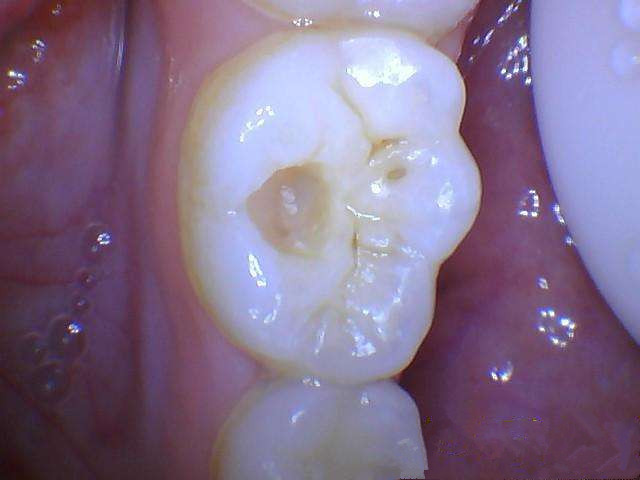

第1阶段:牙齿咬合面有黑线,一般见于大牙,说明开始蛀牙了,牙釉质遭腐蚀,但不痛不痒,一般很难发现。这时候应及时补牙,而不是洗牙。费用大概在300左右。

第2阶段:牙齿上明显龋洞,细菌腐蚀到牙本质,对冷热酸甜敏感,这时候需要是腐质去除进行补牙即可。

第3阶段::牙齿超过一半烂掉,说明已经重度蛀牙,细菌伤及牙髓牙神经,还伴随着剧烈疼痛,牙神经病变这时得根管治疗处理,挽救伤痕累累的牙齿。费用也要上千块。